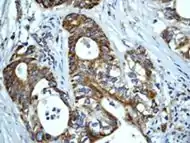

Immunohistochemical staining of paraffin-embedded human breast carcinoma using anti-Hsp60 RabMAb. Click on image for source. http://www.epitomics.com/images/products/1777IHC.jpg